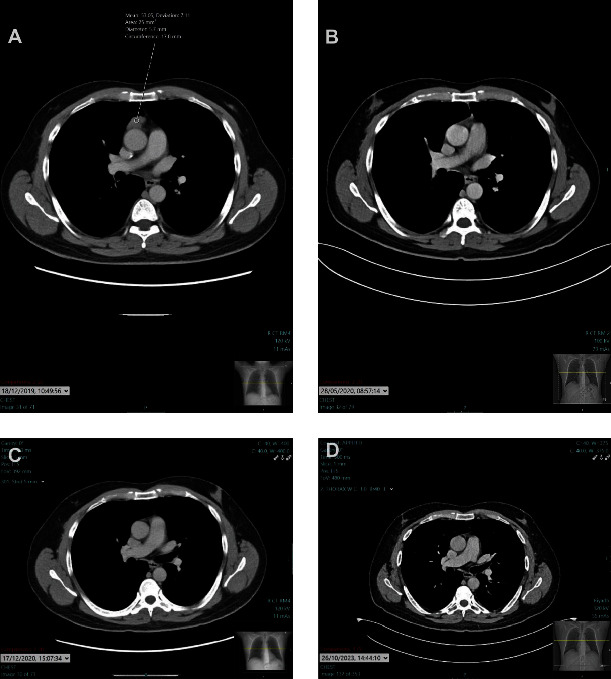

This case report presents a unique clinical scenario of a 58-year-old male suffering from severe refractory myasthenia gravis and concurrent alopecia areata postthymectomy. Myasthenia gravis, a common autoimmune disorder, is characterized by muscle weakness due to autoantibodies targeting neuromuscular junction proteins. Alopecia areata, another autoimmune disease, is often seen in individuals with myasthenia gravis, suggesting a shared immunological basis. The patient's condition was resistant to conventional treatment, and he developed alopecia areata following thymectomy. Despite the challenges in managing refractory myasthenia gravis and the associated alopecia areata, significant improvements were observed following a cortisone taper. This case highlights the potential therapeutic role of cortisone tapering in managing refractory myasthenia gravis and associated alopecia areata. This case also prompts further exploration into the immunological shifts following thymectomy, particularly its potential role in triggering alopecia areata.

Abstract Image